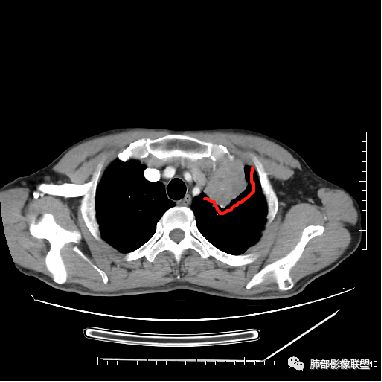

本病例未行冠矢状位重建,未提供连续薄层图像,病灶与支气管情况呈现不满意。

1.中年男性,慢性病程,以咳嗽咳痰为主;

2.双上肺多发病灶,左肺上叶病灶沿血管支气管束分布,由外朝内,以平直收缩为主,周围有斑片渗出,胸膜糊墙,支持炎性病灶或是伴有肿瘤灶可能性。

两上肺发病,多支持结核等感染,但结核基础上伴发肺癌并不鲜见!

3.病灶内多支支气管粘液栓,炎性及恶性均可,但是炎性多于恶性;强化杂乱不均,病灶内小灶坏死比规则,支持炎性肉芽肿病变。

鳞癌病灶如较大,强化常不够显著且多见相对大范围湖泊样坏死。

4. 应仔细观察病变的支气管情况,如果支气管出现腔内结节或阻塞征象,需要提示临床干预,用支气管镜、穿刺等手段来进一步确诊。

5.  本例的焦点主要集中在结核与周围型肺鳞癌的鉴别诊断上!

病灶与大气道的关系未能满意呈现,但如此大范围病灶紧贴胸膜却未见胸壁纵隔组织结构侵犯破坏是不大符合肺鳞癌的生物学行为的。